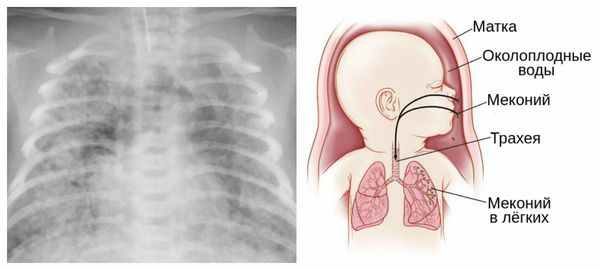

Из-за снижения кровотока в почках плода выделение мочи значительно уменьшается, развивается маловодие. Также изменяется характер околоплодных вод: они теряют прозрачность, становятся мутными, приобретают желтоватый или зеленоватый оттенок из-за примеси мекония — первых фекалий ребёнка.

Для плода большую опасность представляет асфиксия (острая гипоксия) и отслойка плаценты. Нехватка кислорода внутри утробы стимулирует плод выполнить несвоевременные дыхательных движения. Они приводят к заглатыванию вод и возможному воспалению лёгочной ткани — пневмониту. Если в водах есть примесь мекония (первородного кала), то велика вероятность мекониальной аспирации — проникновения содержимого кишечника новорождённого в его лёгкие.

Клиническими проявлениями дистресс-синдрома плода при

перенашивании являются аспирация мекониальных вод и нарастающая внутриутробная гипоксия плода. Смертность при синдроме мекониальной аспирации достигает 60 %о, а перенесенная внутриутробная гипоксия, даже если не приводит к смерти ребенка, способствует возникновению перинатальных повреждений ЦНС [4]. Между тем, перинатальные повреждения ЦНС достигают 60-80% всех заболеваний нервной системы детского возраста, что придает им, безусловно, огромное медико-социальное значение.

В связи с большей зрелостью центральной нервной системы у переношенных плодов повышена чувствительность их к гипоксии и родовым травмам. Этому способствуют также большие размеры головки плода и отсутствие способности её к конфигурации из-за плотных костей черепа, узких швов и родничков. Частыми осложнениями у ребенка являются синдром дыхательных расстройств и пневмопатии за счёт внутриутробной аспирации околоплодных вод и разрушения сурфактанта в, легких переношенного плода.